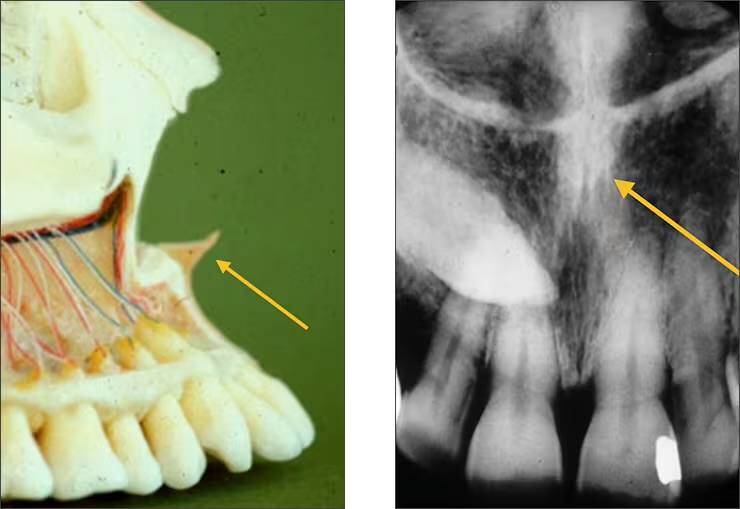

Inverted Y

Depicts where the nasal fossa crosses the maxillary sinus (the boundary between them are shaped like a upside down Y)

Incisive foramen / nasopalatine foramen

Appears between the roots of the central incisor & looks like a round oval less than 1 cm in diameter

Seen on maxillary central incisor PA’s